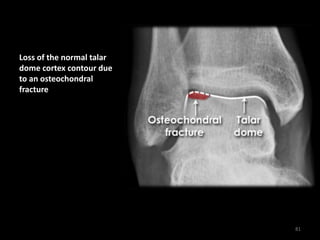

Osteochondral fracture

Loss of the normal talar

dome cortex contour due

to an osteochondral

fracture

81